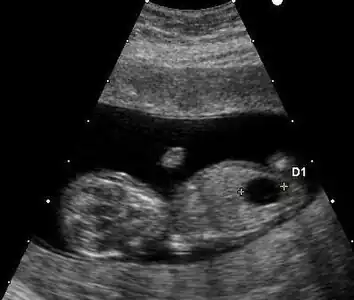

Ultrasound

Prenatal ultrasound can be used to screen for Down syndrome. Findings that indicate increased chances when seen at 14 to 24 weeks of gestation include a small or no nasal bone, large ventricles, nuchal fold thickness, and an abnormal right subclavian artery, among others.[102] The presence or absence of many markers is more accurate.[102] Increased fetal nuchal translucency (NT) indicates an increased possibility of Down syndrome picking up 75–80% of cases and being falsely positive in 6%.[103]

- Ultrasound of fetus with Down syndrome showing a large bladder

- Enlarged NT and absent nasal bone in a fetus at 11 weeks with Down syndrome